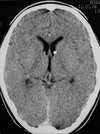

Neurológica - Imagens Flashcards

(52 cards)

aneurisma de artéria basilar, paciente de 2 anos com esclerose tuberosa

esclerose tuberosa

esclerose tuberosa